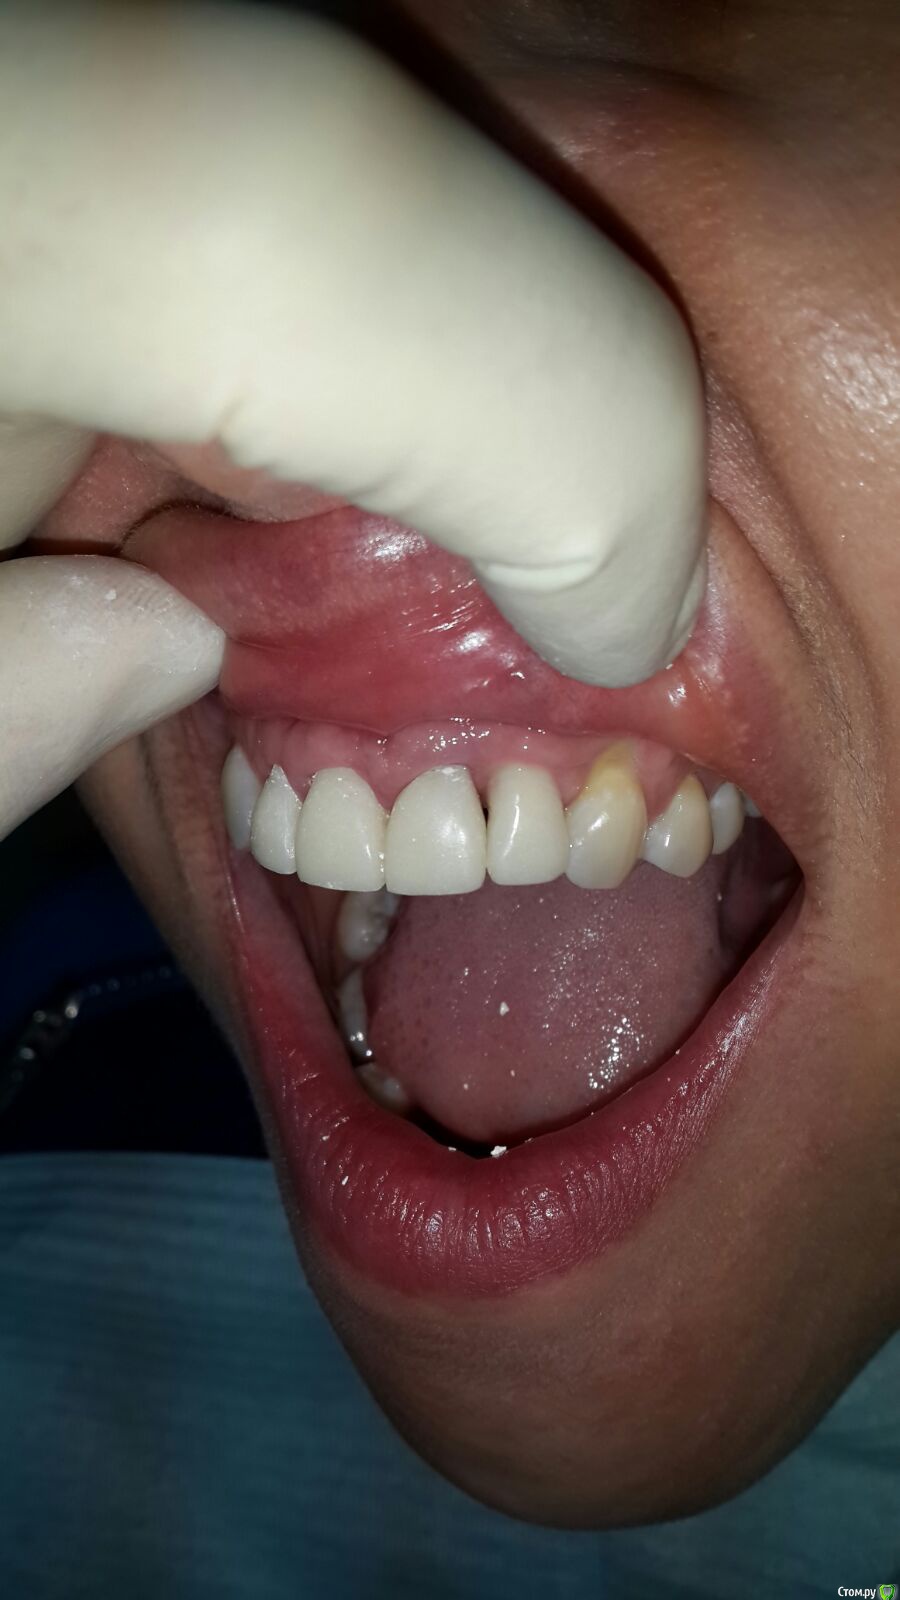

victor57 Опубликовано 21 октября, 2015 Поделиться Опубликовано 21 октября, 2015 (изменено) Привет.сегодня пришла пациентка на этапе.ведем её уже год. Отсутствовал 2.2. Провели аугментацию,потом имплантации.на 12,11,21 коронки уже более 5 лет. Провели одновременно с установкой формироваться убп на 12,11 зубах. Сейчас вопрос по сосочек между 21,22.Ортопед говорит,что времянками по максимуму отдавил.что посоветуете? Изменено 21 октября, 2015 пользователем victor57 Ссылка на комментарий

Дмитрий Никитюк Опубликовано 22 октября, 2015 Поделиться Опубликовано 22 октября, 2015 Снимок нужен. Но и без него видно, что одна из проблем, это близкое расположение имплантата к зубу 21. С мягкими тканями работать нужно, но идеального результат получиться добиться разве что заглушив имплантат. Как более компромиссный вариант можно рассмотреть ортодонтическую коррекцию положения зуба 21. 2 Ссылка на комментарий

carloss Опубликовано 23 октября, 2015 Поделиться Опубликовано 23 октября, 2015 Олег, там гдн нет места, это рядом с клыком и там сосочек пока в полном порядке.. Но чтобы он более менее остался в будущем, стоит заменить абатмент и коронку, и постараться дать там макимально места.. Медиально же место есть Ссылка на комментарий